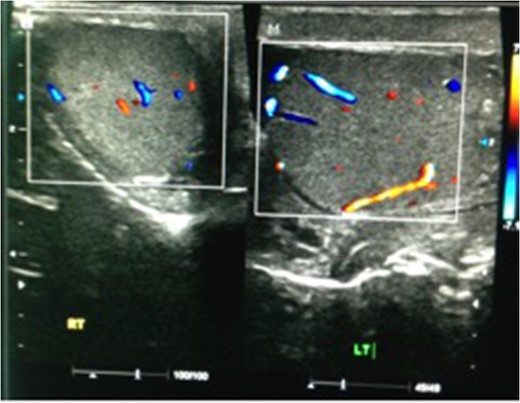

We present a case of a 37-year-old man presented to the Emergency department with a 3-day history of left testicular pain. He had no chronic illnesses and was not immunocompromised. The pain was associated with mild storage lower urinary tract symptoms. He was sexually active but had no previous sexually transmitted diseases and no urethral discharge. He had no history of trauma and had not had any similar episodes before. His examination revealed a swollen tender left testicle; equivocal for testicular torsion. A Doppler ultrasound was done which revealed increased flow to the left testicle with no evidence of testicular torsion (Fig. 1). The patient was subsequently discharged on oral ciprofloxacin, analgesia and instructed to perform scrotal elevation. The patient subsequently presented 6 h later with worsening of his pain and was reviewed and re-imaged with a color Doppler. At this time, imaging findings demonstrated reversal of diastolic flow a feature suggesting impending infarction, along with other features of acute inflammation (Fig. 2). The patient was taken to the operating room and a scrotal exploration was performed. No evidence of torsion was identified. A congested testicle was observed. No evidence of infarction or abscess formation was seen. Day 1 post-operatively the patient continued to have left sided testicular pain, now associated with lower abdominal pain. A KUB ultrasound and a repeat scrotal ultrasound were performed. These demonstrated absent flow in the left testicle (Fig. 3). On repeat exploration a dusky blue testicle was found and a left orchidectomy performed. Testicular histopathological analysis demonstrated features suggestive of acute necrotizing inflammation of the testes and epididymis as well as the spermatic cord and its vessels. Cultures of the urine subsequently showed significant growth of Escherichia coli.

Ultrasound scan showing both testicles at initial presentation, with increased flow on the left side, indicative of EO.